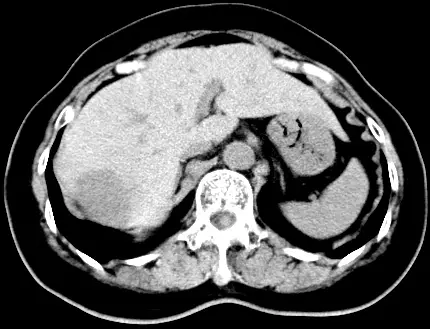

本題提供三張 Dynamic CT 影像,為肝臟右葉 4 cm 腫瘤的三期掃描:

圖二(門靜脈期 Portal venous phase):強化範圍由外往內逐漸填充(centripetal fill-in),周邊強化區域擴大,中央低密度區縮小,整體密度漸升高。